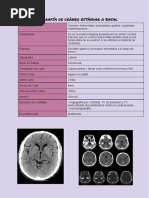

La tomografía axial computada (TAC o TC) permite observar el interior del cuerpo a través de cortes milimétricos mediante rayos X y un sistema informático. Los escáneres de primera generación tardaban 5 minutos por corte, mientras que los de tercera generación, que rotan continuamente alrededor del paciente, pueden completar un escaneo en menos de 10 segundos. La cuarta generación mantiene los detectores fijos mientras el tubo de rayos X rota, logrando tiempos de escaneo menores a un segundo.